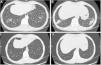

She remained in clinical remission until 4 years ago, when she noticed persistent dry cough, with periods of fever and sputum, and a rise in inflammatory markers. Sequential chest X-rays had migratory pulmonary infiltrates and computed tomography (CT) showed peribronchovascular micronodules, dilated and thick-walled bronchioles with a fluffy tree-in-bud (Fig. 1A, B). The patient was recurrently diagnosed with presumed chest infections and treated with multiple cycles of antibiotics; MTX was suspended and PDN raised to 10mg/day.

Chest computed tomography at diagnosis (A, B) and 8 months after treatment with steroids and clarithromycin (C, D). Peribronchovascular micronodules and dilated and thick-walled bronchioles with a fluffy tree-in-bud similar to “cotton-in-bud” present at diagnosis (A, B), resolved after treatment with steroids in association with 4 months of clarithromycin (C, D).

Due to symptoms’ persistence, with concomitant anorexia and loss of 10kg in 2 months, she was admitted into hospital for further evaluation. She denied smoking habits or occupational/environmental exposures. On examination she had a body mass index of 21kg/m2, pulmonary auscultation with subtle crackles in both lung bases, without arthritis, lymphadenopathies or organomegaly. Pulmonary function tests (PFTs), including carbon monoxide diffusing capacity (DLCO), were normal, without hypoxemia. Complementary exams showed negative viral serology (human immunodeficiency virus and hepatitis B/C), negative serology for acute infection by Mycoplasma pneumoniae, normal serum proteinogram, normal immunoglobulins levels and negative antinuclear antibodies. Abdominal/pelvic CT scan and endoscopy were normal. She was submitted to bronchoscopy with unspecific inflammatory changes; bronchoalveolar lavage had normal cellularity, without identification of any microorganisms, including Mycobacterium tuberculosis. Transbronchial biopsy had nonspecific lymphocytic infiltrate, forming small aggregates, without vasculitis, granulomas or neoplastic tissue. The patient was then submitted to surgical lung biopsy that demonstrated lymphoid follicles with peribronchiolar germinal centers and associated bronchiole constriction (Fig. 2), making the diagnosis of FB. The patient started PDN (0.75mg/kg/day), with clinical and radiological improvement, but one month later she developed steroid-associated neuropsychiatric symptoms and PDN was tapered. However, fever and sputum recurred, without evidence of infection. BF relapse was assumed and the addition of a second drug was discussed between rheumatologists and pulmonologists. Due to the absence of articular activity and considering the previous adverse events experienced by the patient with immunosuppressive drugs and the fear of these drugs to worsen lung disease, clarithromycin (500mg/day) was added for 4 months, with progressive symptomatic improvement and PDN tapering. Four months later complete resolution of chest CT alterations was noted (Fig. 1C, D) and PDN was stopped. The patient remains currently under no treatment for 10 months, without evidence of BF recurrence and no need for further immunosuppression.